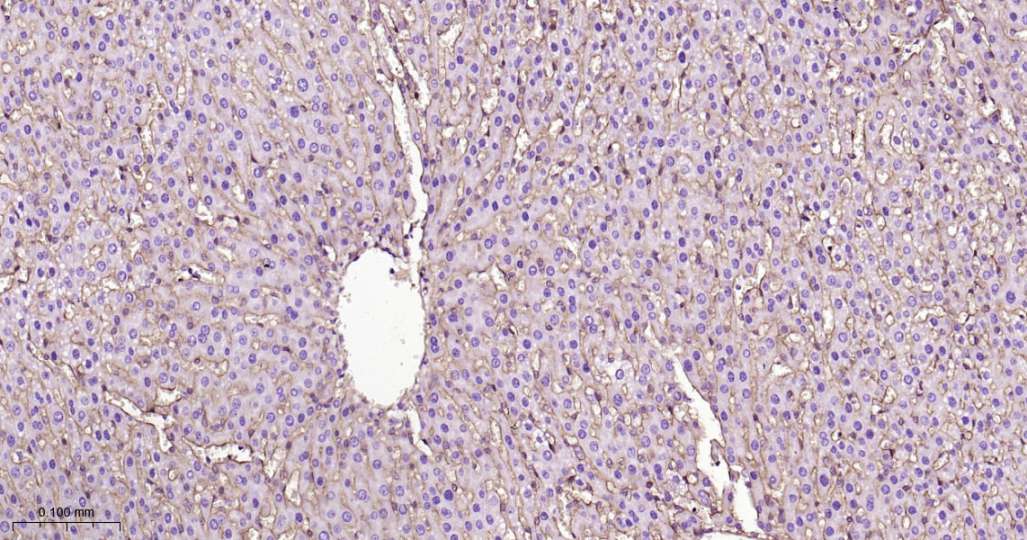

Immunohistochemical analysis of paraffin embedded Rat liver tissue slide using IHC0521 (Integrin beta 1 Kit).